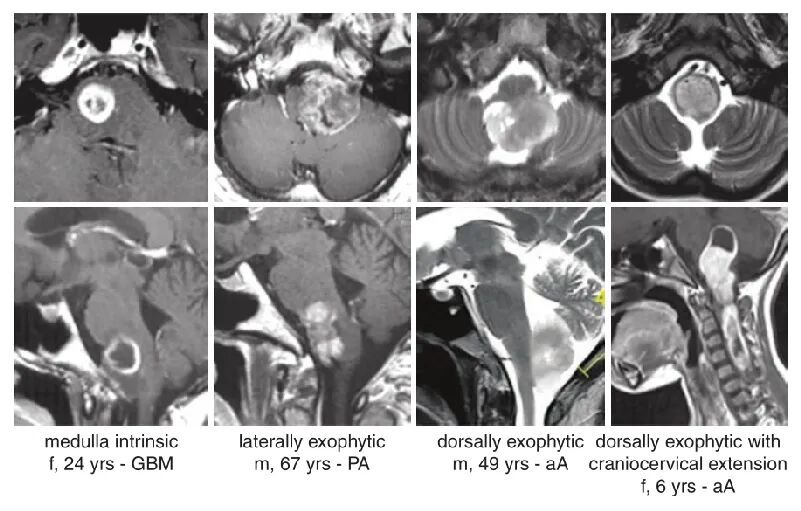

德国巴特朗菲教授总结了临床上遇到的不同性质的延髓胶质瘤,并区分了4种不同的类型。其中,13个肿瘤局限于脑干下部,其他病变在外生性生长,9个肿瘤主要生长在外侧,8个肿瘤向下方延伸从延髓进入脊髓。

▼图:MRI显示延髓区肿瘤的部位与范围代表性图像4列分别为本组4例不同患者。其中,aA为间变性星形细胞瘤,GBM为胶质母细胞瘤,PA为毛细胞星形细胞瘤。